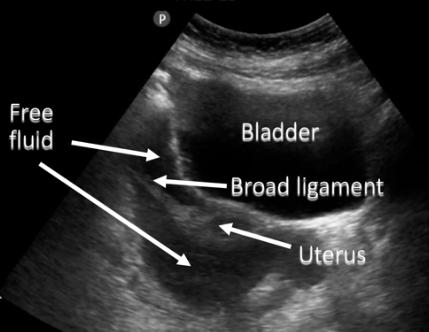

平时体检,B超报告会提示“盆腔积液10-30mm”或者“少量盆腔积液”。

女性在站立或平卧时,子宫和直肠之间的间隙是盆腔的最低点(也叫后陷凹或道格拉斯窝),盆腹腔的分泌的液体都在这里聚集。

所以,几乎每个女性都会有盆腔积液,一般高度都在3cm以下,如果没有任何不舒服的症状,是不需要瞎花钱治疗的。

1. 积液量特别多:B超显示积液量远大于3cm,或者除了后陷凹,前陷凹、髂窝等到处都有积液;